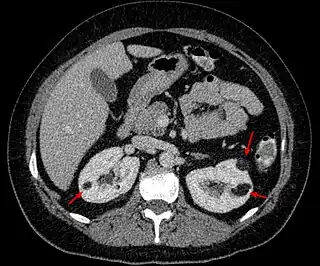

![]() Angiomiolipomas en ambos riñones (flechas) en una tomografía axial computarizada. | ||

Este tumor benigno es poco habitual; es el doble de frecuente en mujeres que en hombres. Se suele diagnosticar en adultos jóvenes de forma casual, en un estudio de imagen realizado por otro motivo en el 80% de los casos. Menos frecuentemente (15%) se diagnostica a raíz de una complicación hemorrágica denominada Síndrome de Wünderlich. Se suele detectar con ecografía, como una masa renal de aspecto hiperecogénico (debido a su contenido graso) pero el diagnóstico definitivo (para diferenciarlo de un tumor maligno) se establece con TAC con contraste radiológico o Resonancia Magnética sin contraste. No está indicada la biopsia por el riesgo de sangrado (al tener en su composición tejido vascular). Una vez establecido el diagnóstico de angiomiolipoma, el seguimiento se puede realizar con ecografía sin necesidad de otras pruebas de imagen. Se puede presentar de forma aislada, pero hay casos asociados a la esclerosis tuberosa o a la linfangioleiomiomatosis en cuyo caso los angiomiolipomas están presentes en ambos riñones.